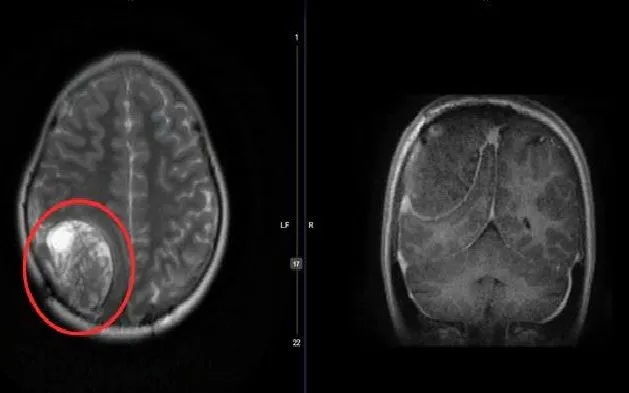

Thời gian gần đây, bệnh nhi xuất hiện triệu chứng đau đầu tái diễn, kèm khối u sưng vùng đầu. Kết quả chụp cộng hưởng từ cho thấy khối u vùng hố chẩm phải tái phát, kích thước khoảng 7,2 × 5 × 5 cm, có dấu hiệu xuất huyết trong u và xâm lấn xoang tĩnh mạch – khiến việc xử trí trở nên đặc biệt khó khăn.